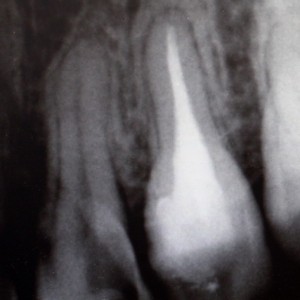

Root Canal Therapy

Root canal therapy refers to a treatment procedure that dentists use to save and preserve an infected tooth. It commonly involves three stages of treatments: Nerve Removal, Root Preparation, and Root Filling. The actual number of treatment sessions varies according to the complexity of root anatomy.

Crowns are often indicated because root-canal-treated teeth are prone to fracture and need coronal protection against potential leakage from within the mouth.